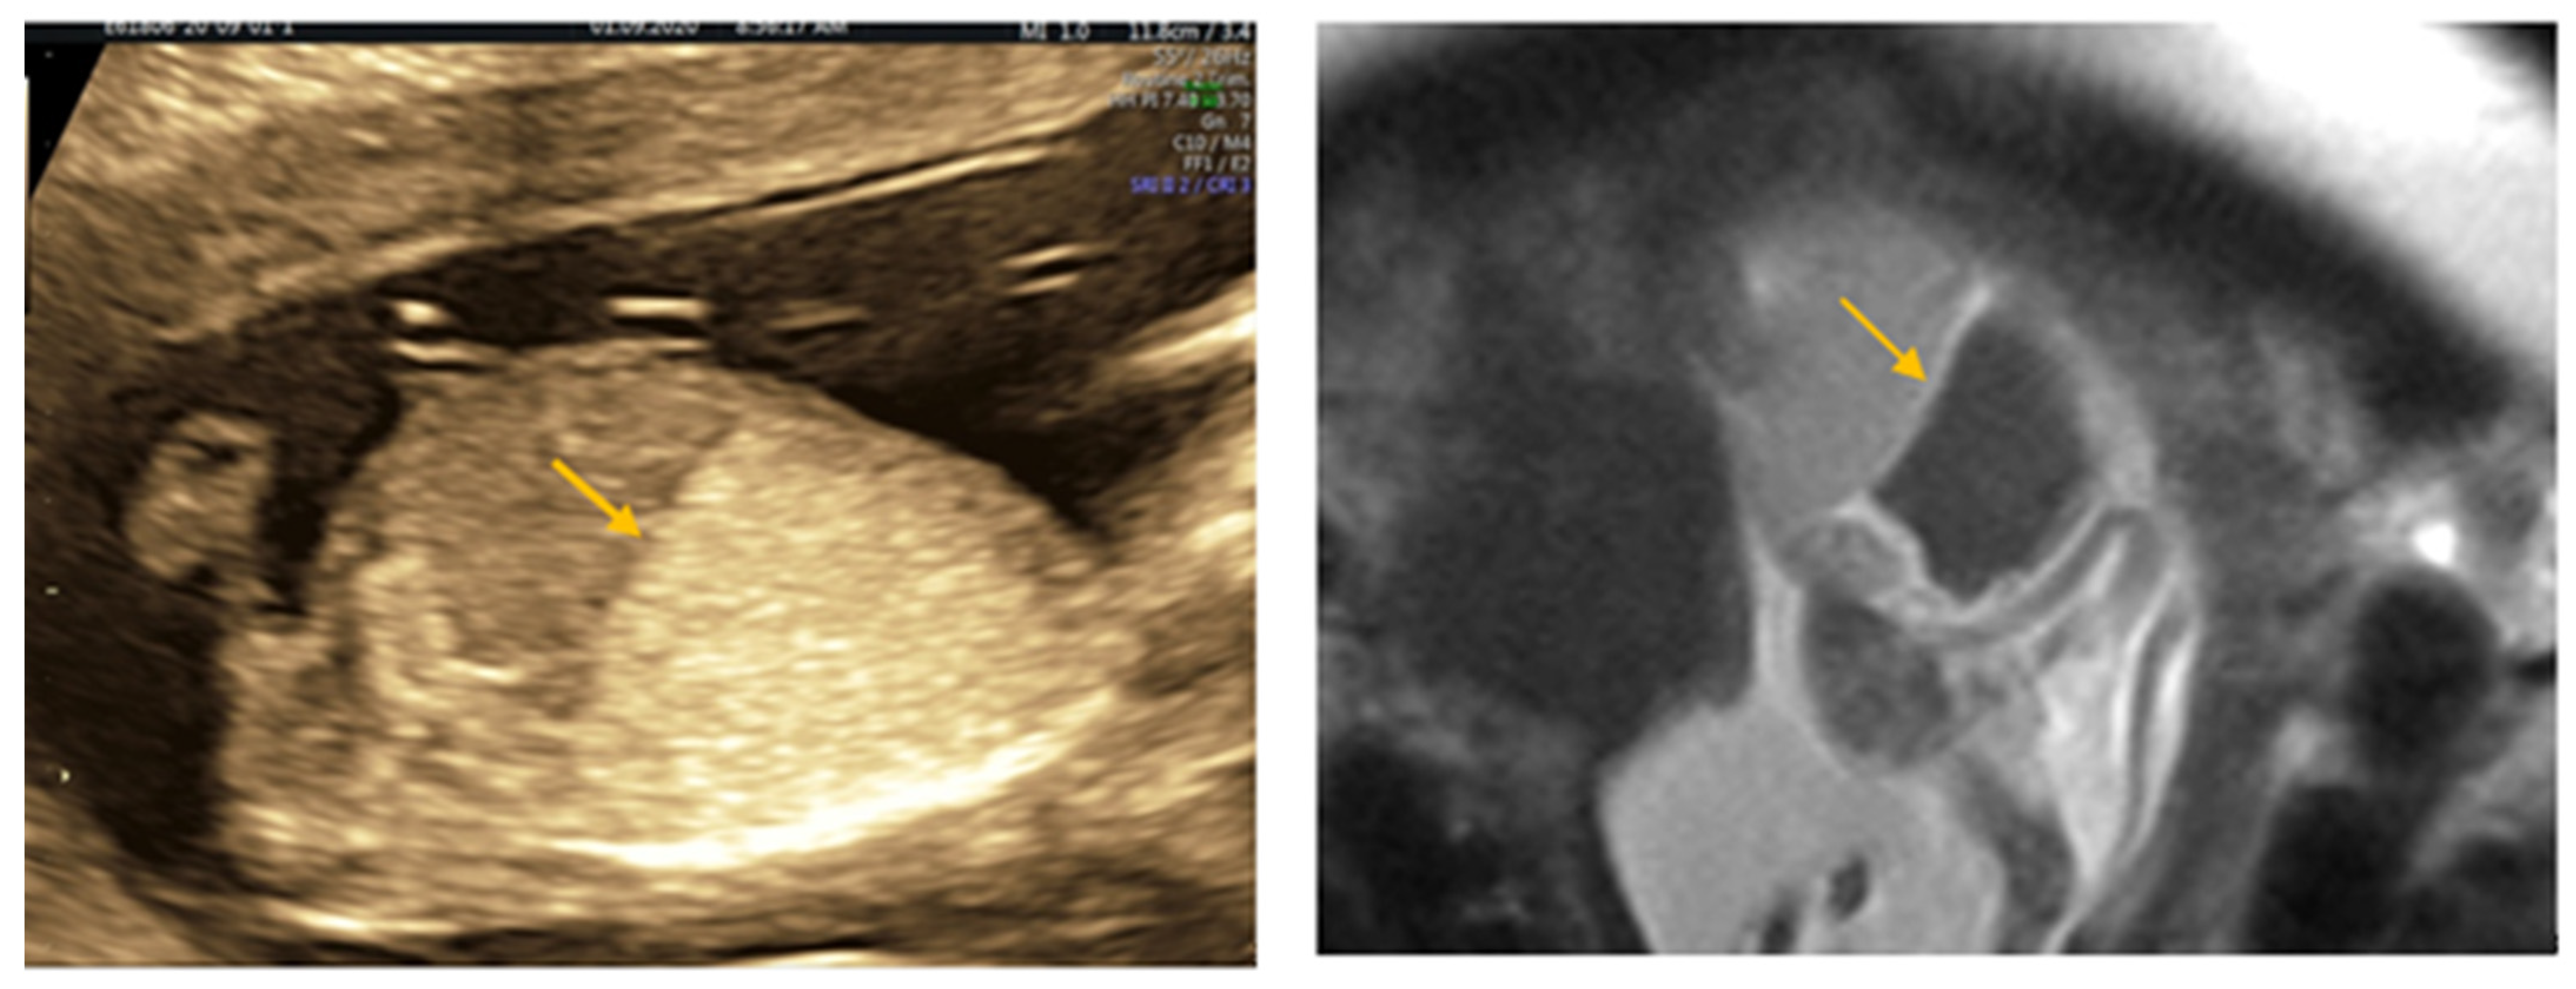

2. Case Report